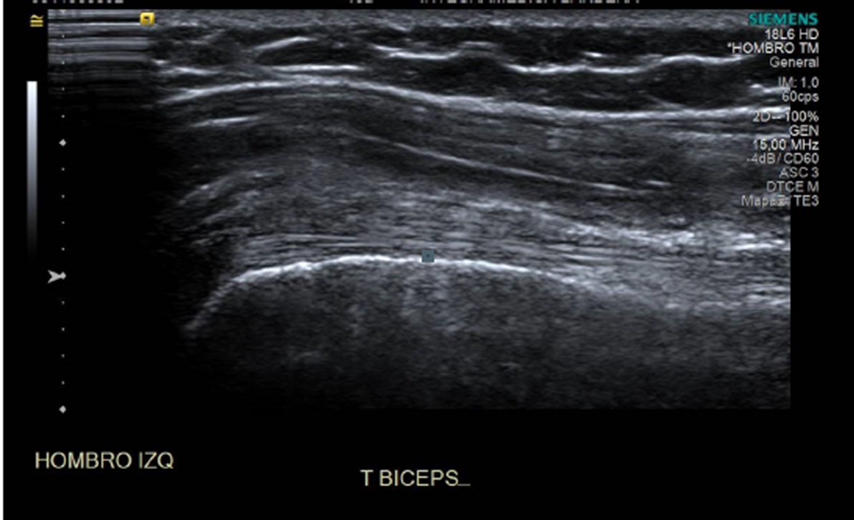

• En tercio proximal del tendón del bíceps hacia anterior se observa imagen ovalada, isoecogénica, heterogénea, de bordes bien definidos, sin señal Doppler. Sugerente de calcificación.

• El tendón del biceps presenta patrón fibrilar y ecogenicidad conservada y se encuentra bien situado en la corredera bicipital, con distensión de su vaina y calcificaciones en relación a la vaina tendinea.

• Tenosinovitis bicipital con calcificaciones en relación a la vaina tendinea.